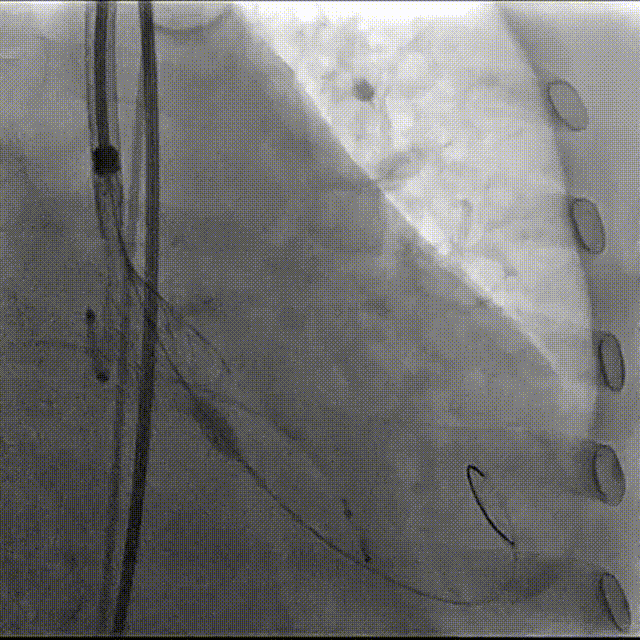

第一次瓣膜定位,心脏再次停跳,按压复律

第二次完全释放

球囊后扩

最终造影